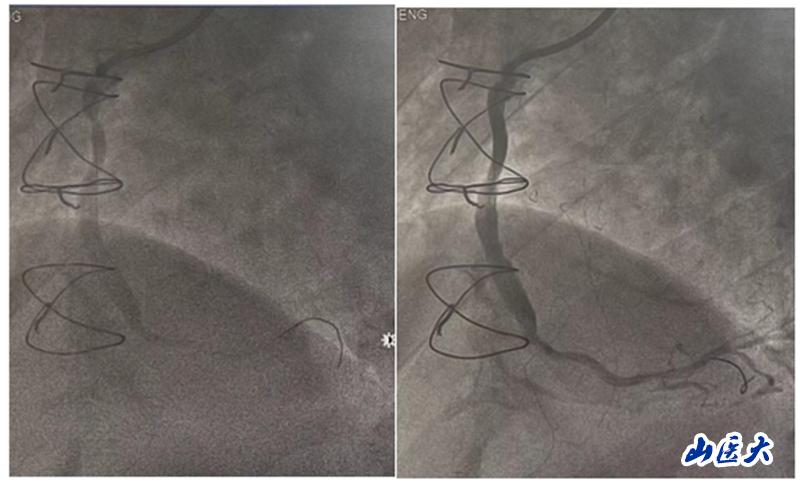

在手術中,團隊發現患者的前降支、回旋支口部和右冠脈近段均存在閉塞情況,升主動脈-右冠脈橋血管近端狹窄約90%。團隊決定對升主動脈-右冠脈橋血管進行介入治療。他們快速準確地判斷了病變血管的范圍,并選擇了激光消蝕輔助以及合適的球囊和支架進行干預治療。手術后,患者安返病房,未再出現胸悶及氣緊等不適癥狀。